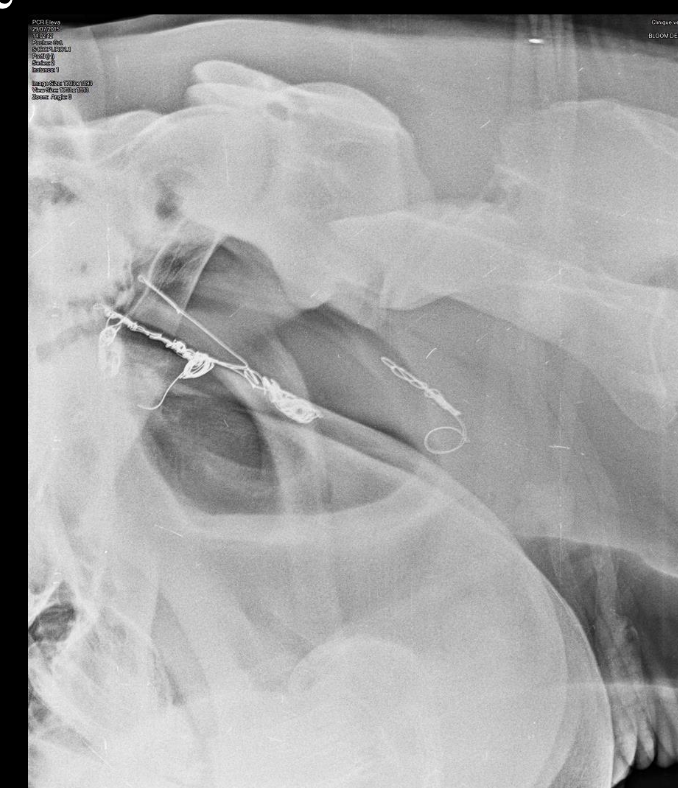

quel est le traitement de la mycose des poches gutturales (5)

A

1. Ligature de carotide commune -> arrêter le saignement en urgence au champ

2. Embolisation transartérielle (coil

ou plug)

3. Cathéter à ballonnet (Fogarty

catheter)

4. Salpingopharyngostomie

5. traitements complémentaires

-> pour enlever la mysose, il faut retirer l’apport sanguin aux poches gutturales

Quelle procédure est considérée comme le “gold standard” pour la mycose des poches gutturales

embolisation transartérielle

-> occlusion optimale non invasive

21

Q

V ou F: L’embolisation transartérielle est une procédure non sélective

faux: procédure sélective, on sélectionne l’a. carotide interne, carotide externe ou maxillaire spécifiquement.

22

V ou F: L’embolisation transartérielle est une procédure couteuse, mais qui réussi dans 90-100% des cas

Nommez 2 complications de l’embolisation transartérielle

• possible atteinte de l’artère oculaire (cécité)

• embolie gazeuse